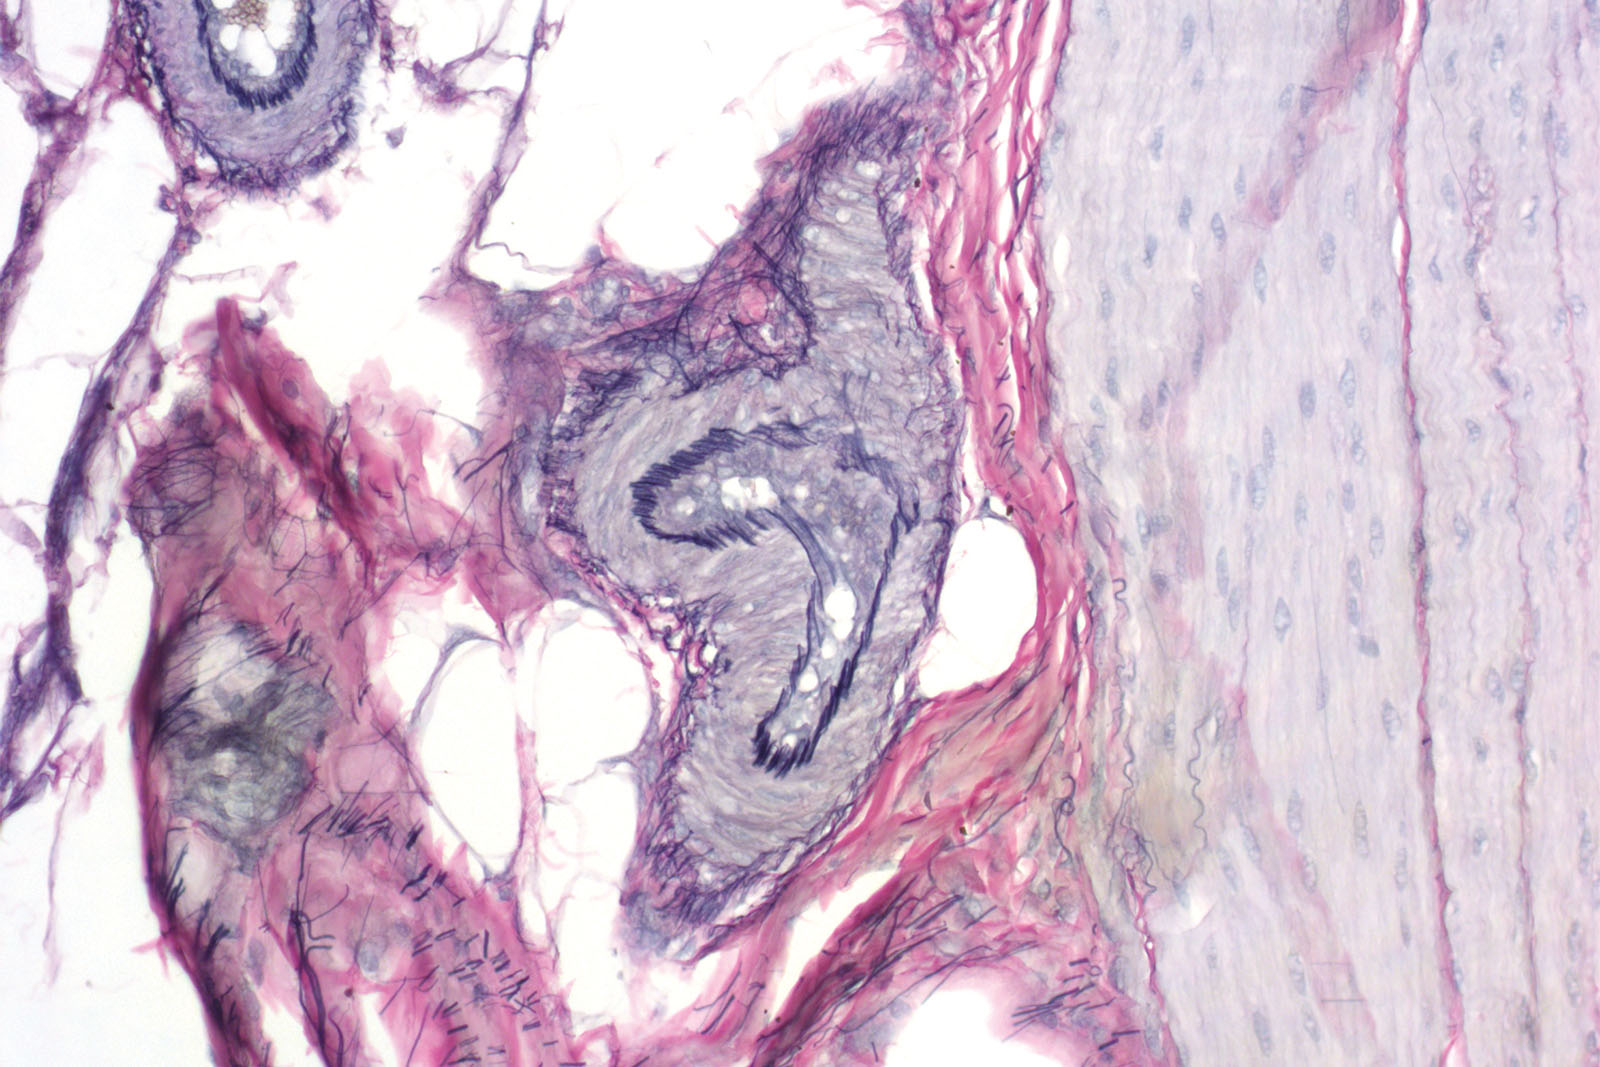

Verhoeff kit is used primarily for staining elastin. However, it may be used for staining muscle fibers, as well as collagen. Elastic fibers consist of elastin polymers and elastic microfibrils that make up a 3D network in an extracellular matrix inside connective tissue (skin, elastic cartilage, vascular walls, lung tissue and in vocal cords). It can be used instead of the Weigert-Van Gieson kit. Visualization of elastic fibers is especially important in cases of emphysema (elastic tissue atrophy), arteriosclerosis (thinning and loss of elastic fibers), and many other cardiovascular diseases.